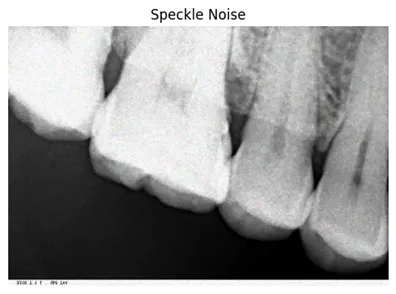

3.3. 散斑噪声

散斑噪声在通过超声波或合成孔径雷达获取的图像中很常见,会导致随机的亮度或暗度变化。它模糊了细节,改变了像素强度,并为图像分析和解释带来了挑战。